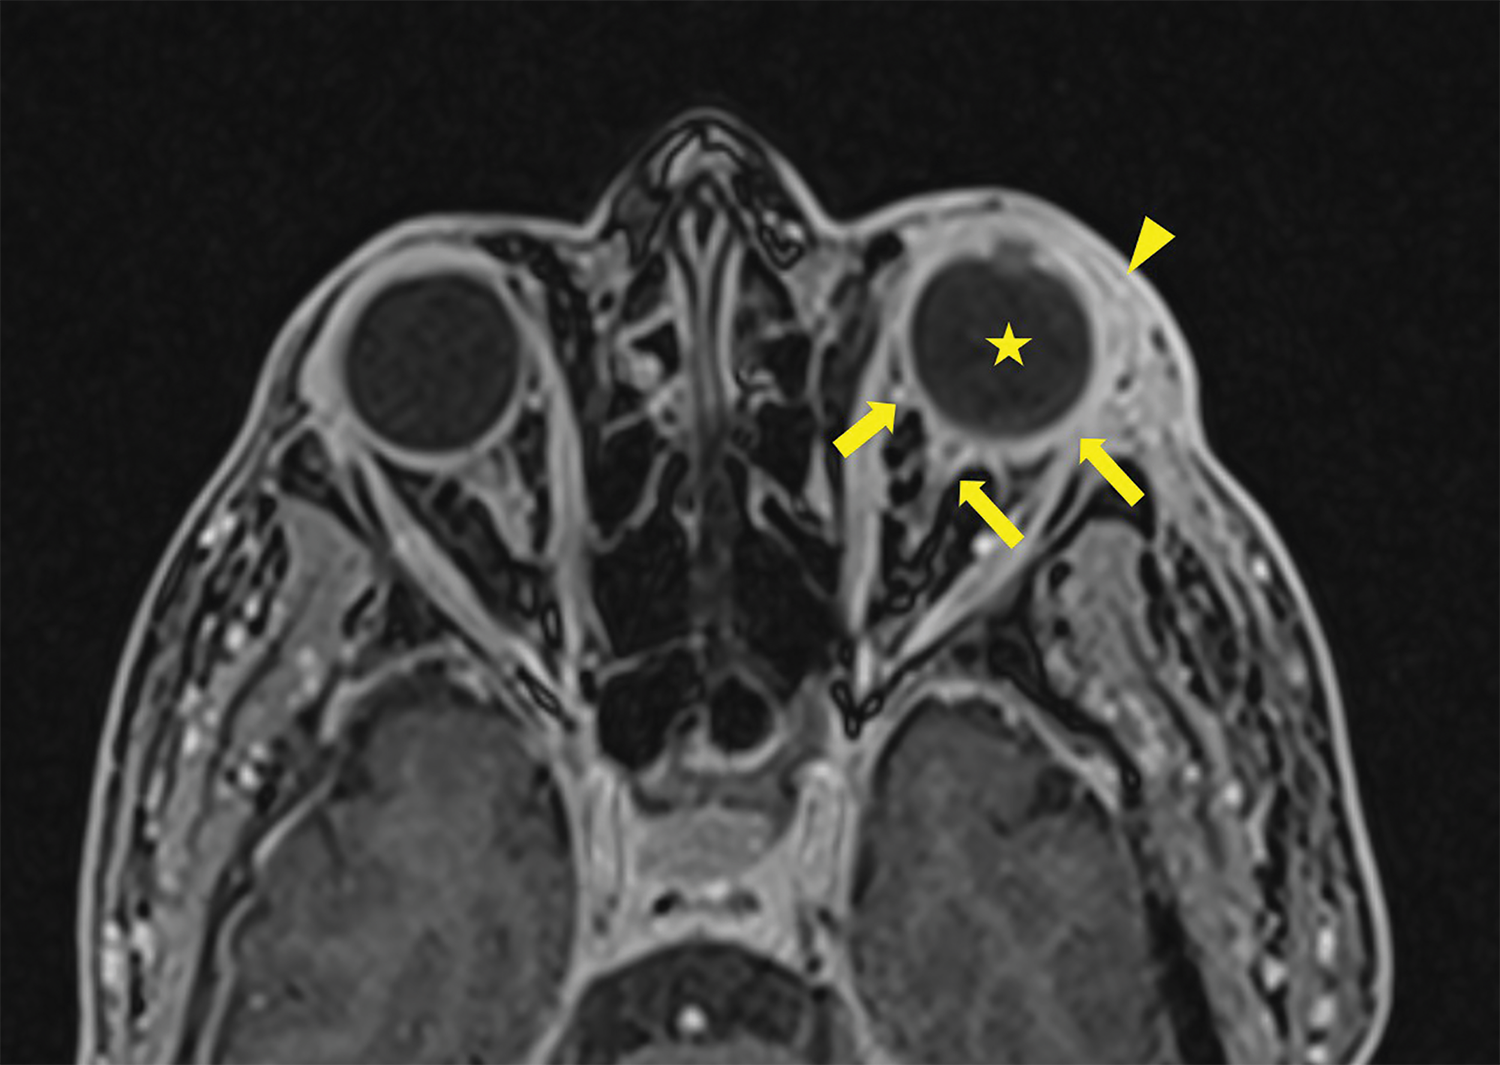

Figure 1

3D T1 Dixon Sequence showing pre‑septal enhancement (arrowhead) with an increase of the sclera enhancement as well as the junction between the left ocular globe and the optic nerve (arrows). Note the slight increase in T1 signal of the vitreous body (star).